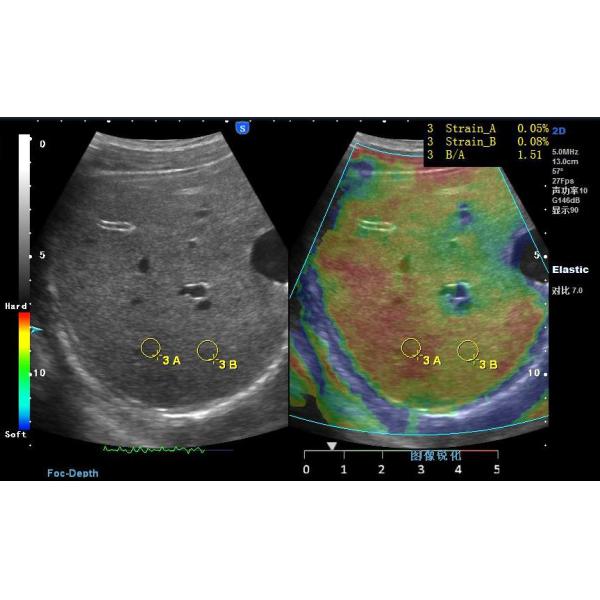

Figure 1. Strain image of healthy liver using freehand elastography

Figure 2. Strain image of healthy kidney using freehand elastography

Figure 3. Clinical strain images of confirmed (a) inflammation lesion; (b) benign and (c) malignant breast tumor

2. Freehand elastography

Motion tracking of manual compression or breathing

induced movement generates a strain image

representing the elasticity of the underlying tissue. Statemed